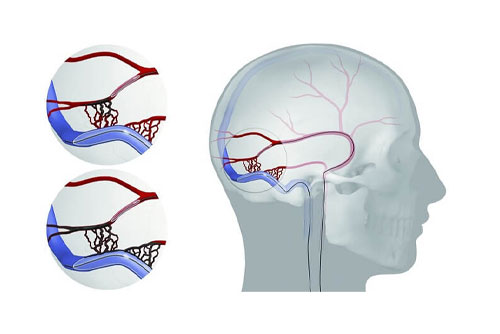

Neuro Intervention

Interventional Neuro Radiology

Cerebral Angiogram

Stroke Management

Mechanical Thrombectomy Stroke